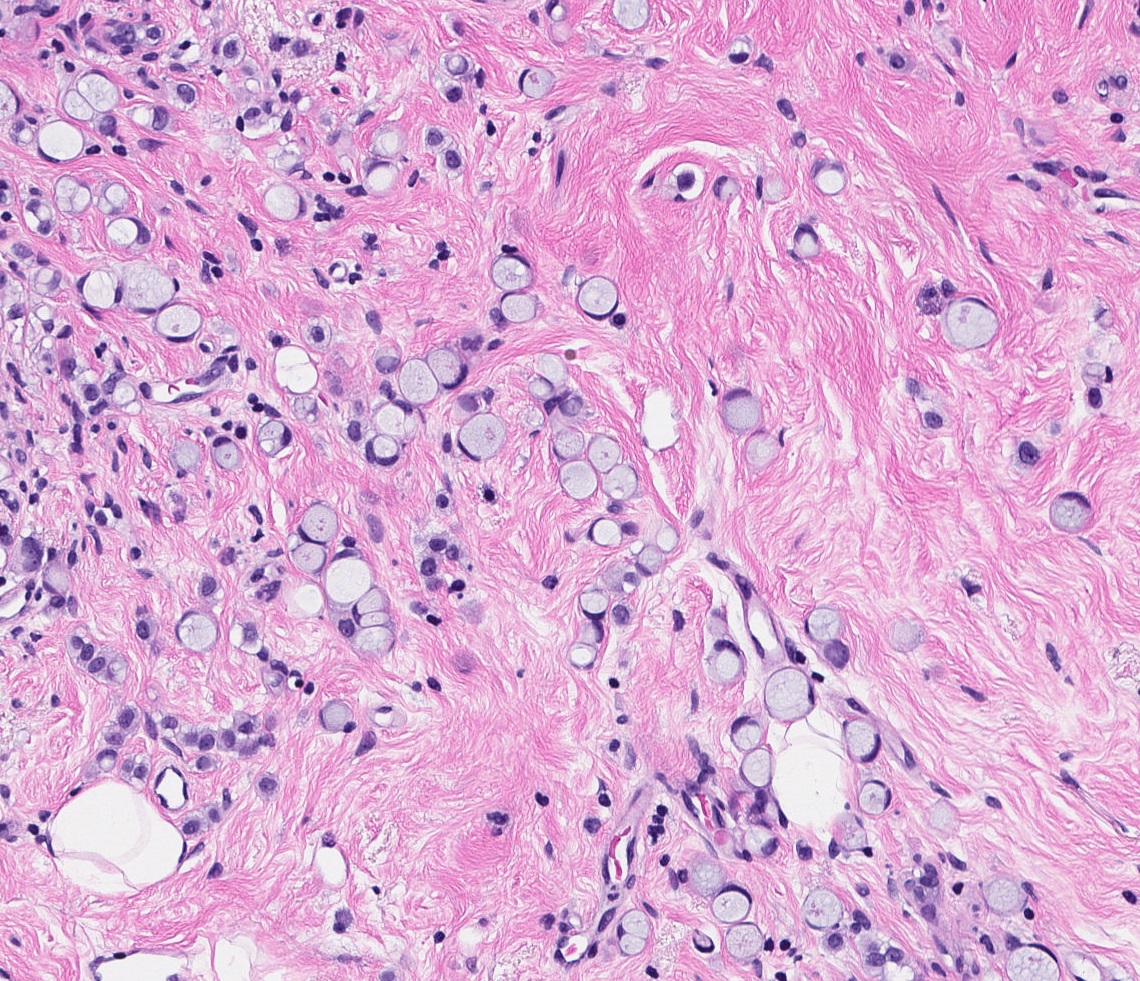

- Other (nonclassic) patterns of lobular carcinoma

- Histiocytoid:

- Foamy cytoplasm resembling histiocytes

Microscopic (histologic) images